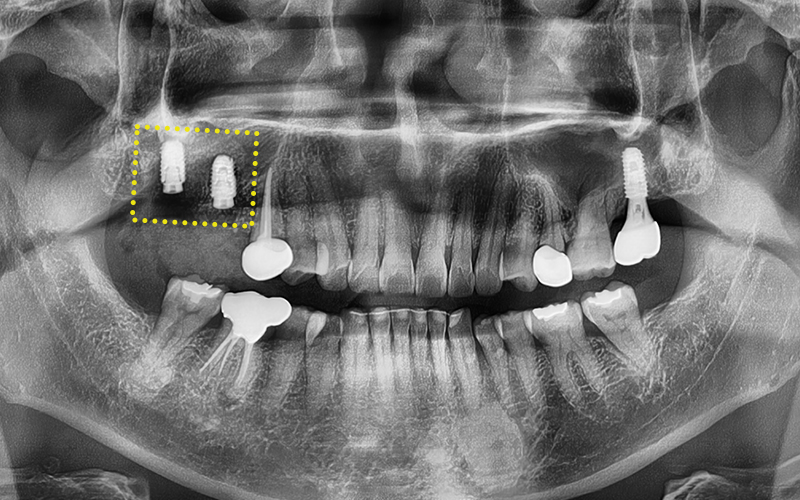

At the one-month check after placement,

we confirmed that there were no particular issues,

and decided to wait while the implant integrated well with the jawbone.

✅ Second surgery completed

After confirming that the implant had integrated well with the jawbone,

we proceeded with the second surgery,

and

After taking impressions, (left image)

we attached a custom abutment. (right image)